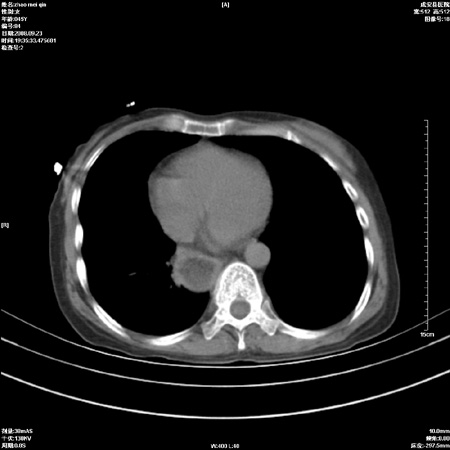

标题: CT15861:女 60 外伤后1小时 胸疼 [打印本页]

标题: CT15861:女 60 外伤后1小时 胸疼

外伤后1小时 胸疼 是外伤后引起的吗?

食道扩张明显下端逐渐变窄,倒像贲门失迟缓

未除外食道异物。如食道石长时间受阻。

考虑术后改变(胸腔胃),建议询问病史.

不除外贲门占位梗阻

非外伤性改变,典型的贲门失迟缓症

食道扩张明显下端逐渐变窄,大量食物存留,象贲门失迟缓症。